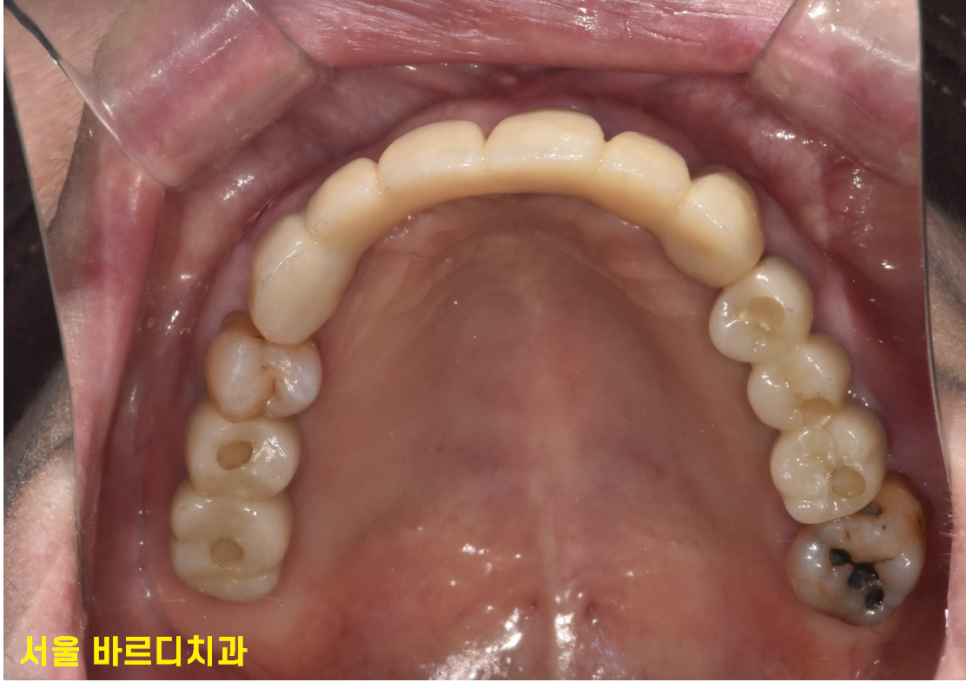

240430

13개의 임플란트 식립 후

전체적인 치아 치료 완료된 사진입니다.

맨 처음 상태가 기억나지 않을 정도이시죠~?